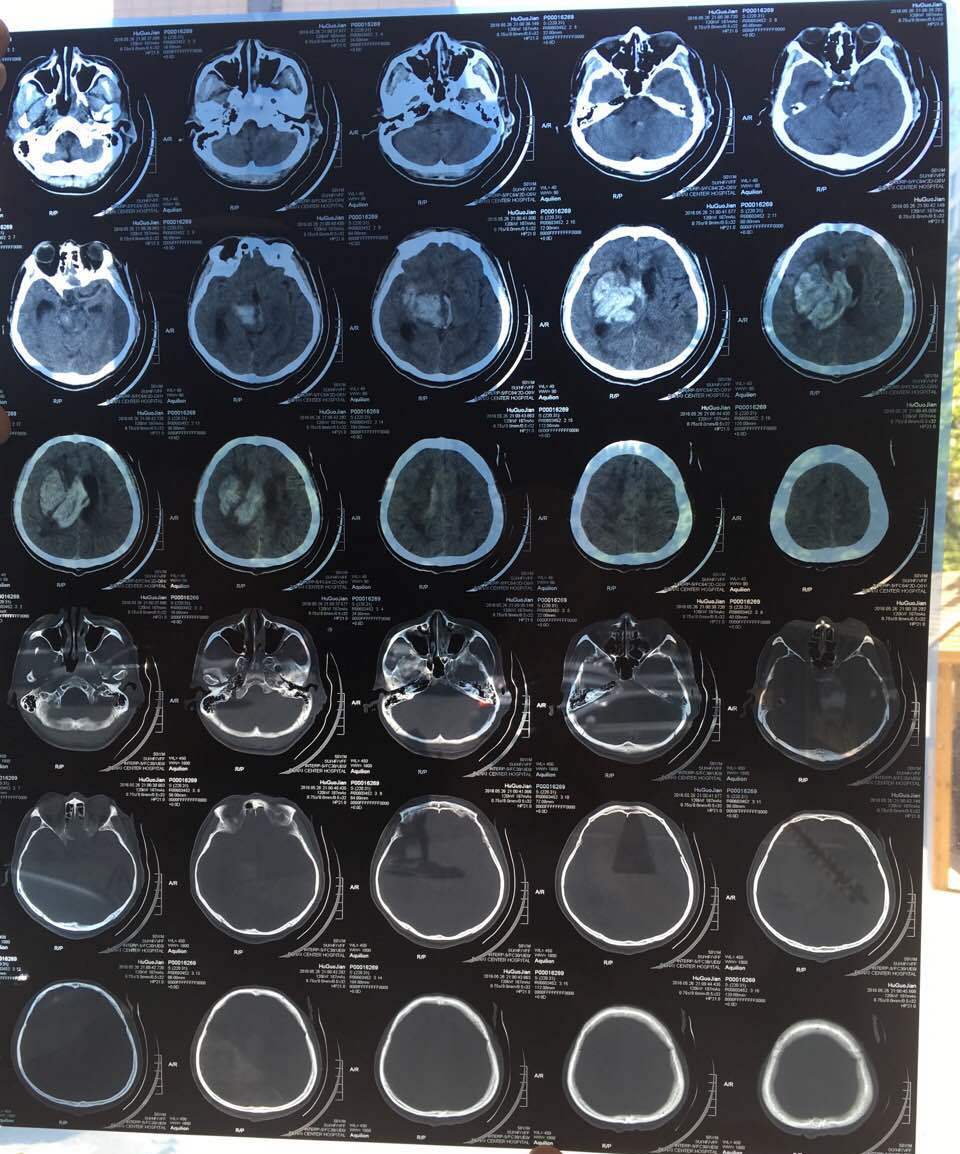

胡国舰的脑CT检查

五月二十六日晚上八点,胡国舰出现昏迷,被送到本溪中心医院抢救。当时做了头部CT检查,发现颅内出血量有一百多毫升。二十七日早上七点零五分,联系上家属,只告诉家属说胡国舰出现昏迷,快速赶往本溪中心医院。当日十点三十分家属赶到本溪中心医院,看到胡国舰已经命悬一线,经过商量和咨询,已对胡国舰做开颅手术,现已七天。